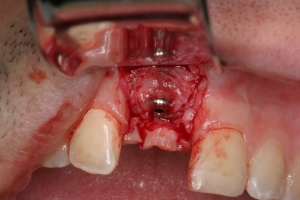

ביצוע ההשתלה עם עיבוי העצם (אוגמנטציה)

קיבוע ממברנה מעל תחליף העצם (הממברנה היא מעין "גדר הפרדה" או מעין פלסטר קטן המגן על אזור תחליף העצם ומאפשר לתאי העצם להתחדש ללא הפרעה)